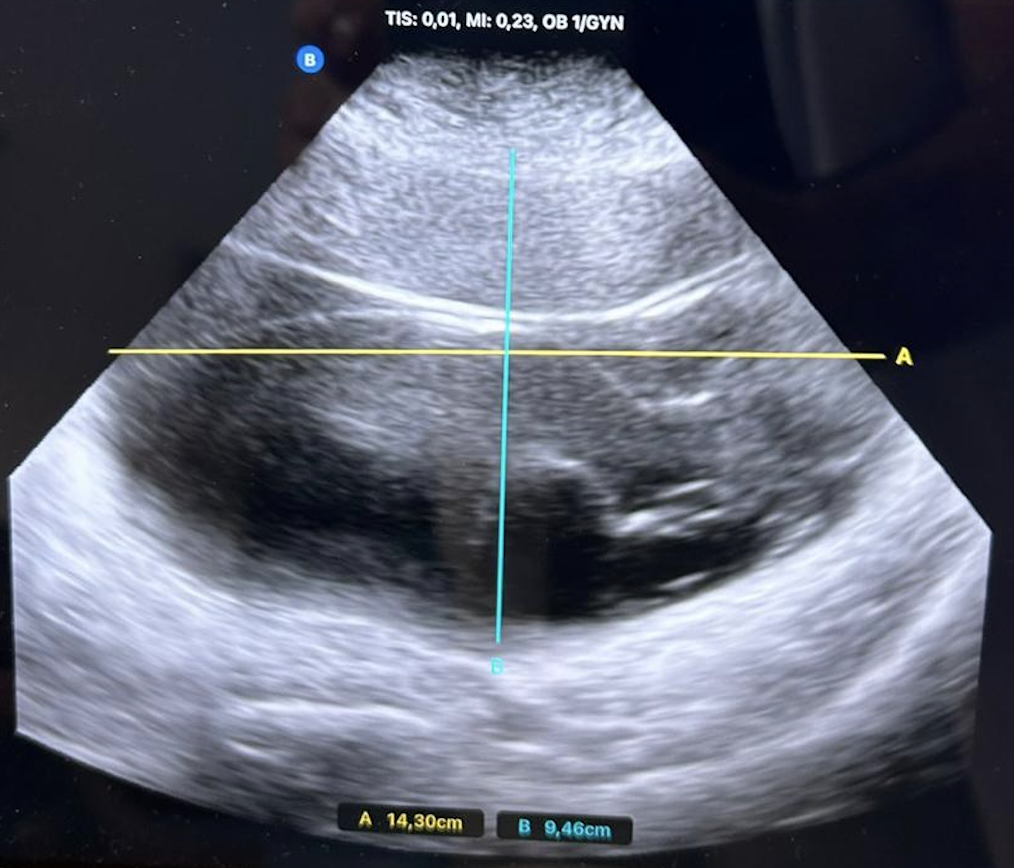

• Ecografía clínica abdominal: Se visualiza cavidad heterogénea y bien delimitada de unos 14,3 x 9,5 cm, con algunos septos en su interior, no capta Doppler. En este caso no visualizamos bien cavidad uterina.

TAC y RNM abdomino-pélvico que describe quiste anexial izquierdo de 10 x 17 x 16 cm sugerente de cistoadenoma mucinoso. Marcadores tumorales negativos. Biopsia endometrial negativa.

• Juicio clínico: Cistoadenoma mucinoso.